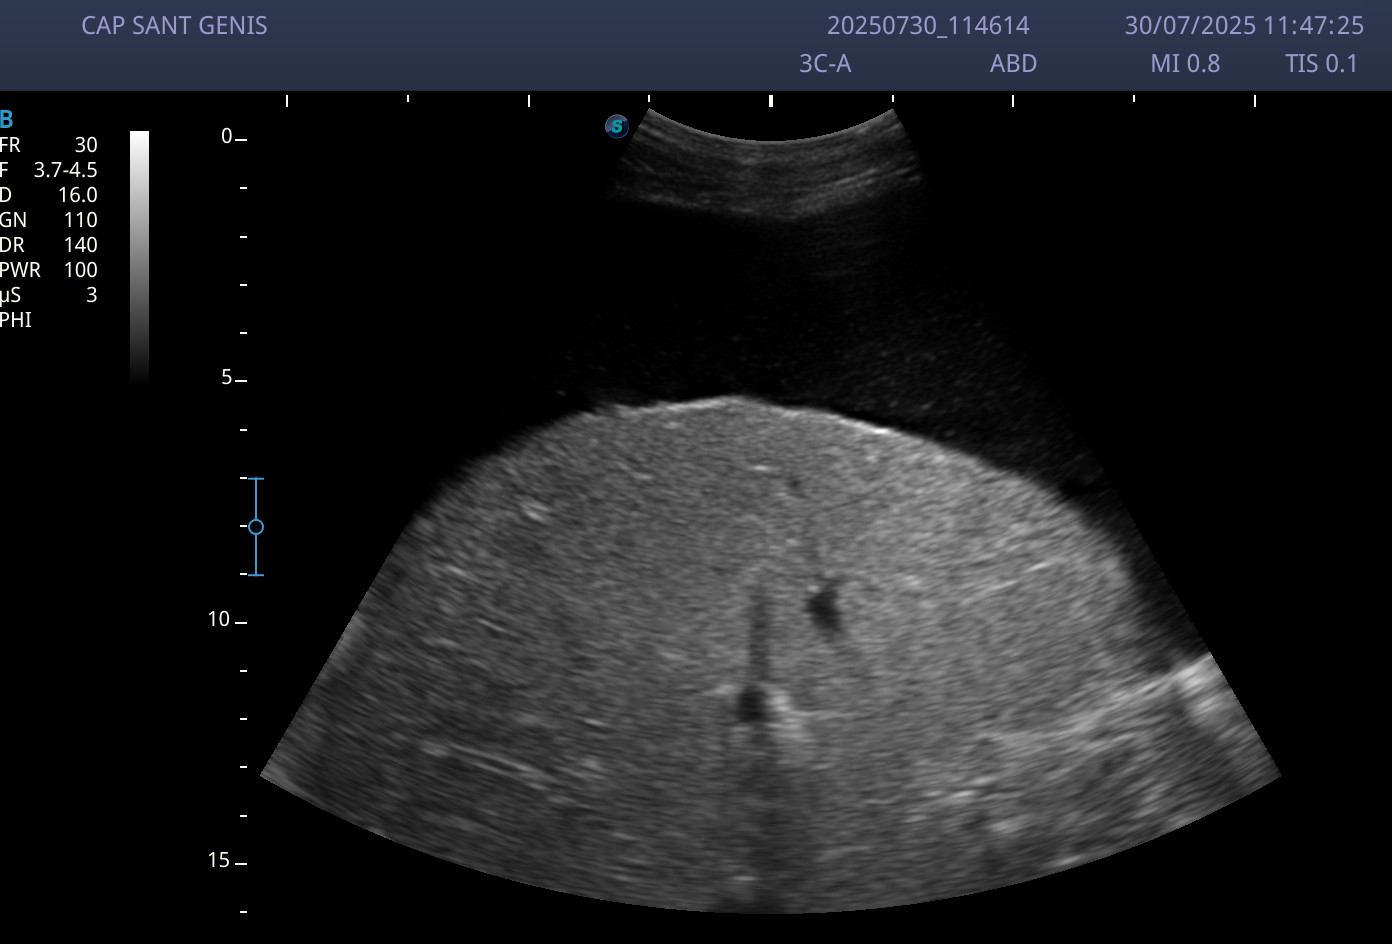

Ecografía abdominal: abundante ascitis perivisceral, y sobre todo a nivel perihepático.

Se trata de un paciente, que aunque tenía historia de patología cardíaca, presentó una clínica que en principio, parecía más de etiología abdominal, y la ecografía resultó clave para reorientar el origen de cuadro que presentaba el paciente.